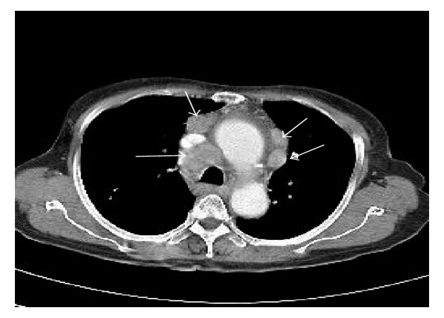

- Whole body imaging (CT, MRI, or PET scan) to determine affected lymph nodes.

- Large intrathoracic tumor mass